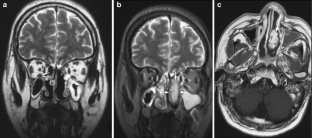

Fig. 3